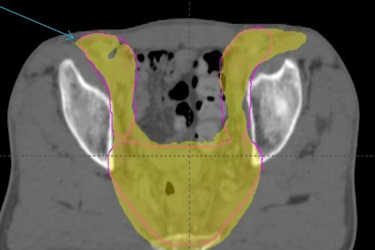

Πριν την θεραπεία ο ασθενής υποβάλλεται σε Αξονική Τομογραφία σχεδιασμού, όπου τοποθετείται σε συγκεκριμένη θέση θεραπείας. Μετά ακολουθεί σχεδιασμός της θεραπείας, προσδιορίζεται η περιοχή ακτινοβόλησης, ο όγκος στόχος και οι κρίσιμες δομές που πρέπει να προφυλαχτούν. Η θεραπεία γίνεται καθημερινά σε 28-30 συνεδρίες. Με την χορήγηση της IMRT τεχνικής μειώνεται η δερματική τοξικότητα, η αιματολογική τοξικότητα, οι παρενέργειες από το πεπτικό και το ουροποιητικό σύστημα.(εικ. 1,2)

ΚΑΡΚΙΝΟΣ ΤΟΥ ΠΡΩΚΤΟΥ IMRT –dose painting (προστασία του εντέρου)